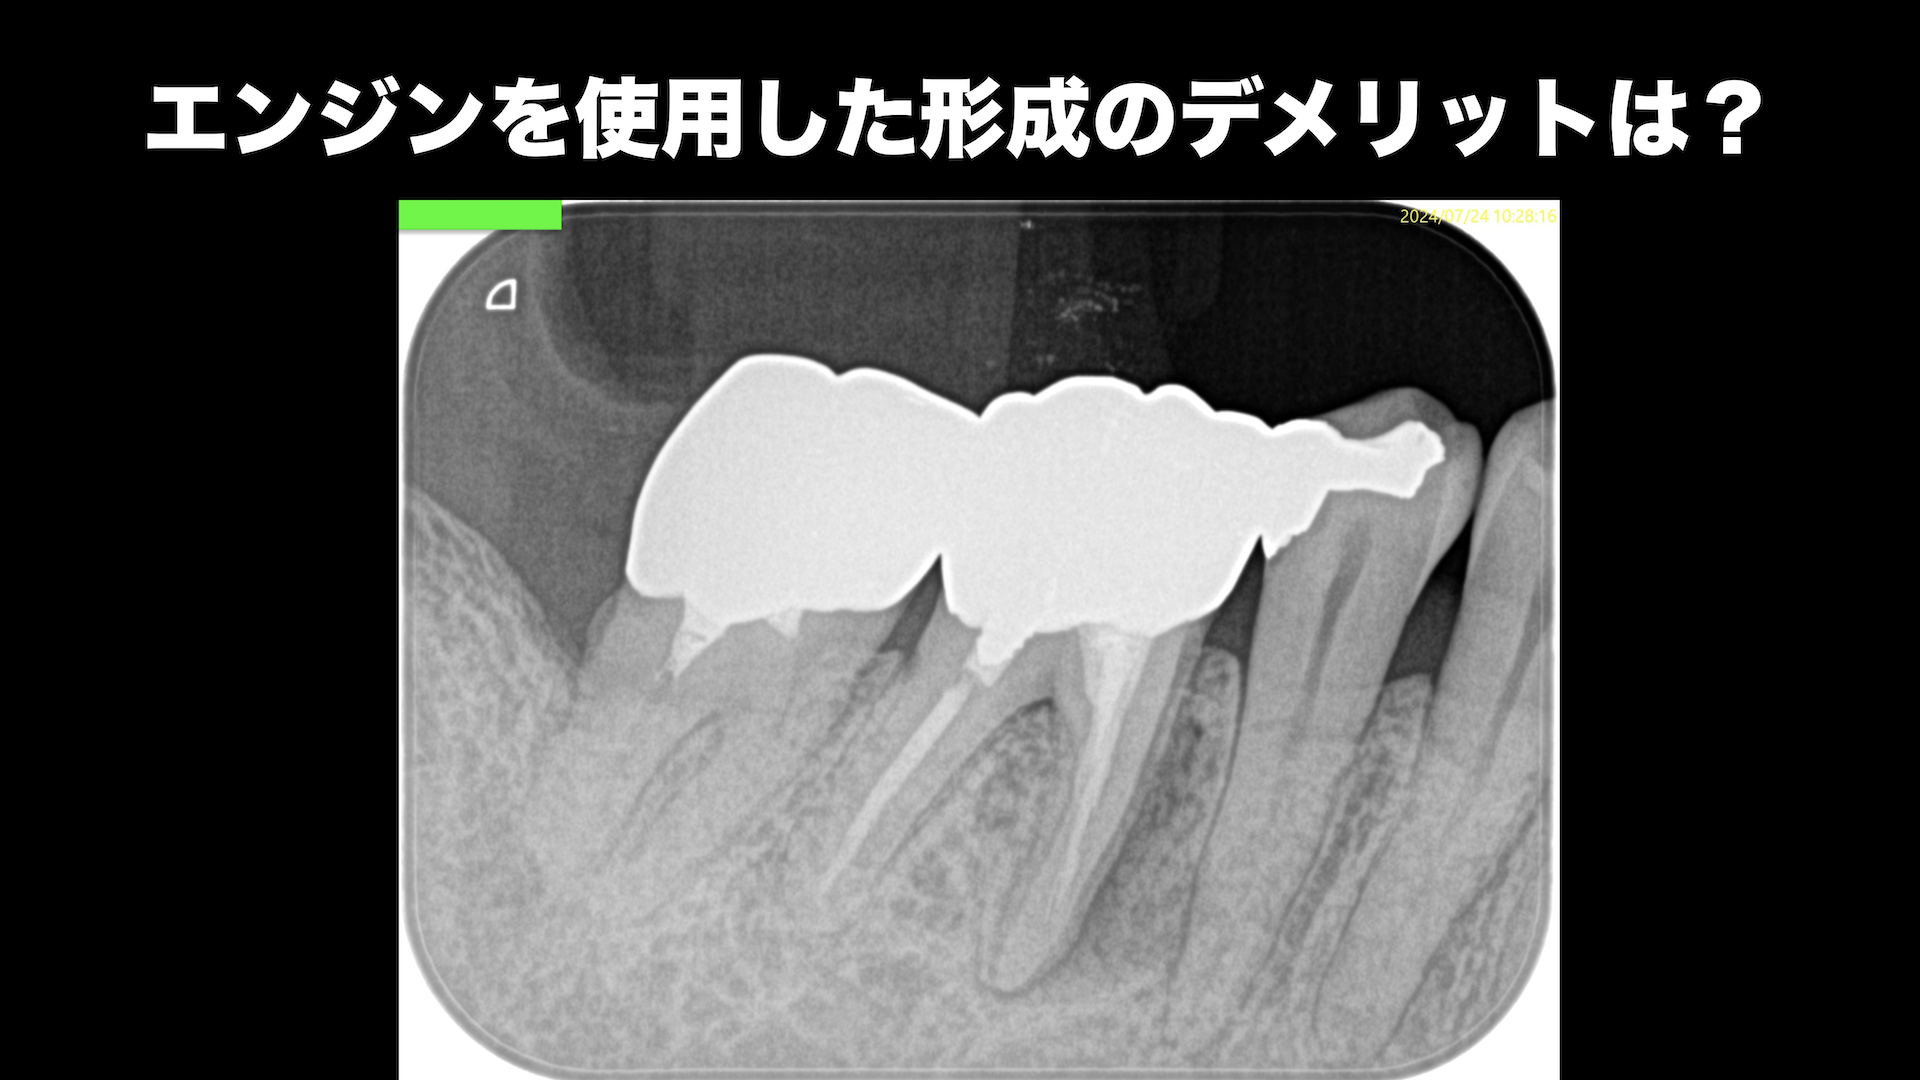

このような絵が出た時に、

アンダーだな…気落ちしてはいけない。

穿通した部分でファイルを止めて試適しPAを撮影すると…

それはあながち間違った位置に存在していないと言うことが客観的にわかる。

では、毎度ファイル試適を撮影するのか?と言えば、それは一人一人の臨床家に任される話だろう。